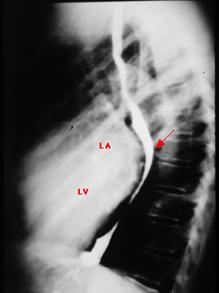

3. Rx. poate arata:

o silueta cardiaca mitrala,

largirea AS (PA, OAS, LS),

dublu contur dr.,

calcificari mitrale sau de AS,

VS mare sau mic,

semne de hipertensiune veno-capilara:

redistributie venoasa lobara sup,

edem interstitial,

linii Kerley exprima staza limfatica (A-la hil, B-la baza SM stransa, C-intre),

edem alveolar,

epansament pleural.

hemosideroza,

calcificari

pulmonare,

infarct pulmonar,

alte boli pulmonare

asociate.